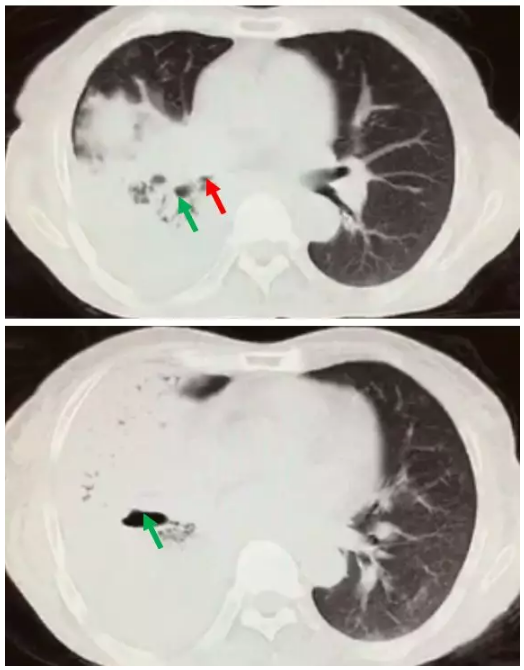

cl2763:支气管痰栓